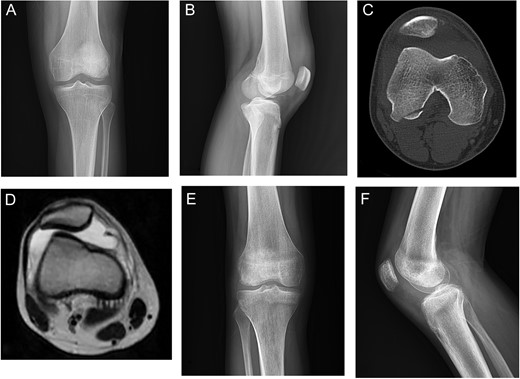

A 19-year-old male came with right knee pain and effusion after a non-contact injury of the knee during a football game. The knee had marked effusion with tenderness over the medial border of the patella. Radiography showed large OCF in the weight-bearing area of the lateral femoral condyle [Fig.1Aand B]. CT scan showed bony fragments from the medial border of the patella [Fig. 1C]. Three months after surgery, radiography showed complete healing of the injury with the full knee range of motion (ROM) [Fig. 1D and F].

Case 1. A and B Radiography showing lateral femoral condyle OCF. C, CT scan showing OCF and patellar avulsion fragment.D and E, 3 months postoperative radiography showing complete union.